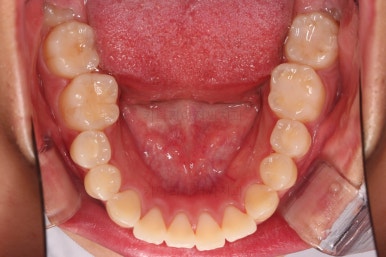

1. 초진 시 입안의 모습 평가

부산연산역치아교정 키다리아저씨치과에 처음 내원했을 당시의 입안의 모습이비다.

앞니 약간, 어금니쪽 약간 삐뚤어진 것, 그리고 위아래 앞니가 약간 뻗쳐 보이는 양상 이외에는 매우 가지런해 보여서 교정치료를 굳이 왜 하시려고 하지? 라고 생각될 정도의 치열 상태였습니다.